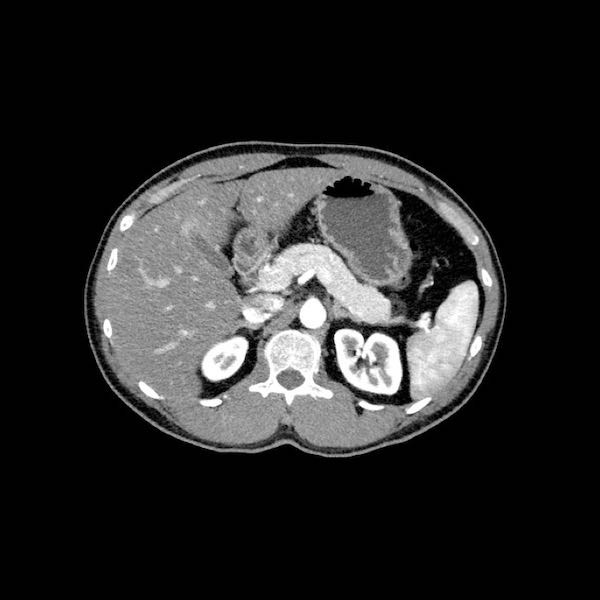

Đánh giá giai đoạn tại chỗ cần được thực hiện bằng CT tụy chất lượng cao, bao gồm thì động mạch muộn và thì tĩnh mạch cửa.

Ung thư biểu mô tuyến tụy thường biểu hiện là một khối giảm tỷ trọng, kém mạch máu, được nhận thấy rõ nhất ở thì động mạch muộn. Đây cũng là thì tốt nhất để đánh giá giải phẫu động mạch nhằm phát hiện các biến thể và hẹp mạch.

Thì tĩnh mạch cửa là tốt nhất để phát hiện di căn gan cũng như phát hiện hẹp và xâm lấn tĩnh mạch.